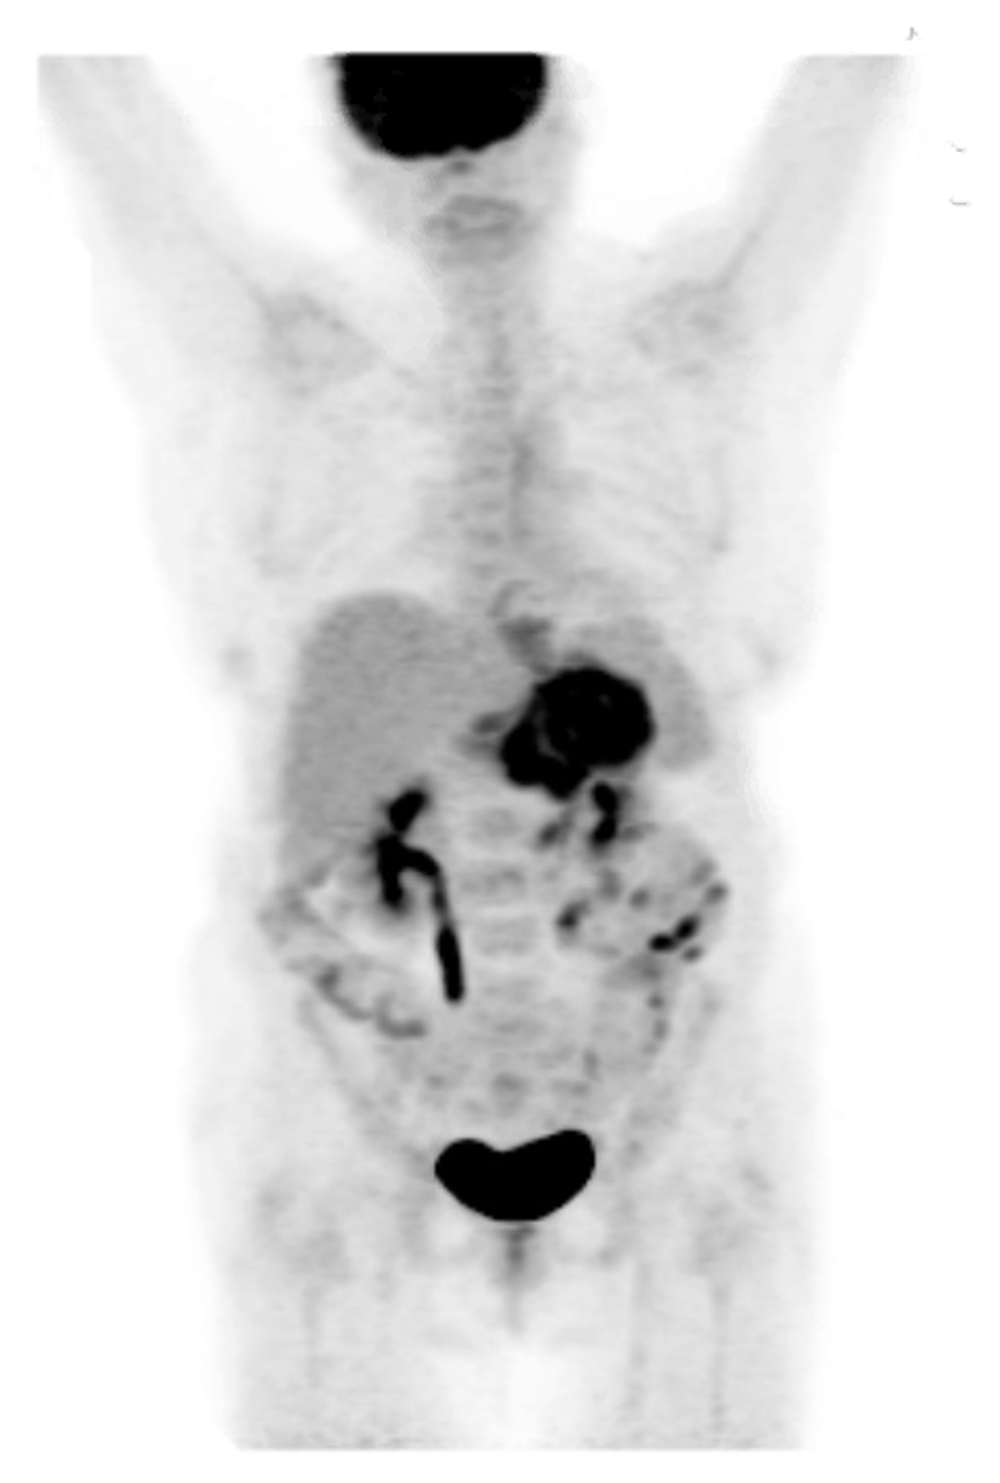

Microscopically, antral mucosa demonstrated mild chronic gastritis. Histopathology revealed a diffuse-type, invasive poorly differentiated adenocarcinoma. IHC staining was only positive for pancytokeratin. The malignant-appearing cells lacked immunoreactivity for synaptophysin, CD45, and HER2 (Figure 3). Together with histopathology and this IHC profile gastric adenocarcinoma was confirmed. She underwent a positron emission tomography (PET) scan for staging. The PET scan showed a localized but advanced gastric neoplasm not associated with any regional PET-avid lymphadenopathy. No obvious metastatic disease was present (Figure 4). Thus, she was diagnosed with locally advanced Stage IB gastric adenocarcinoma (Figure 5).

PET from skull to mid-thigh reveals extensive, diffuse hypermetabolism throughout the gastric wall compatible with a PET-avid infiltrating gastric neoplasm. No metastatic disease is apparent. Scattered areas of contrast uptake within the bowel are likely physiologic and limit evaluation for lesions. Contrast uptake within the brain and genitourinary system are physiologic.